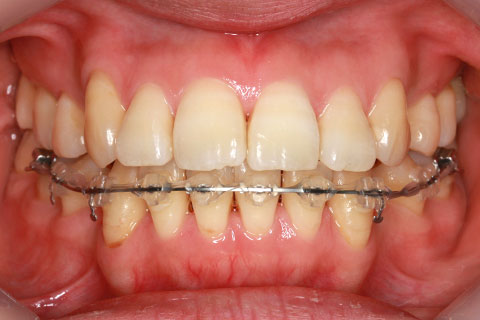

矯正期間24ヶ月

ハーフリンガル矯正3(上の歯のみ舌側矯正で治療)

治療前

治療中(開始直後)

治療中(開始半年後)

治療後

- 年齢・性別

- 25歳女性

- 治療期間

- 2年0ヶ月

- 抜歯

- 上下4番抜歯

- 治療費

- 110万円

- 備考

- 治療内容

- 施術の副作用(リスク)

- 表側矯正と比較して、力学的な操作性が複雑なため、ボーイングエフェクトを起こしやすい。